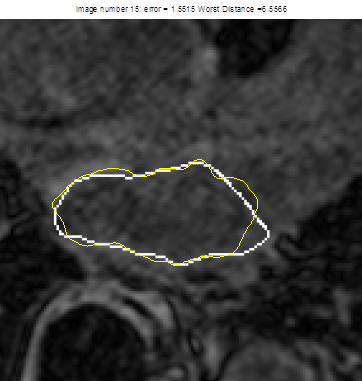

File:Heart1topology.png

Heart1topology.png (362 × 381 pixels, file size: 78 KB, MIME type: image/png)